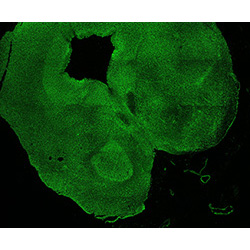

11PCW

DAPI

11PCW human midbrain

MAP2

SOX2

Merged